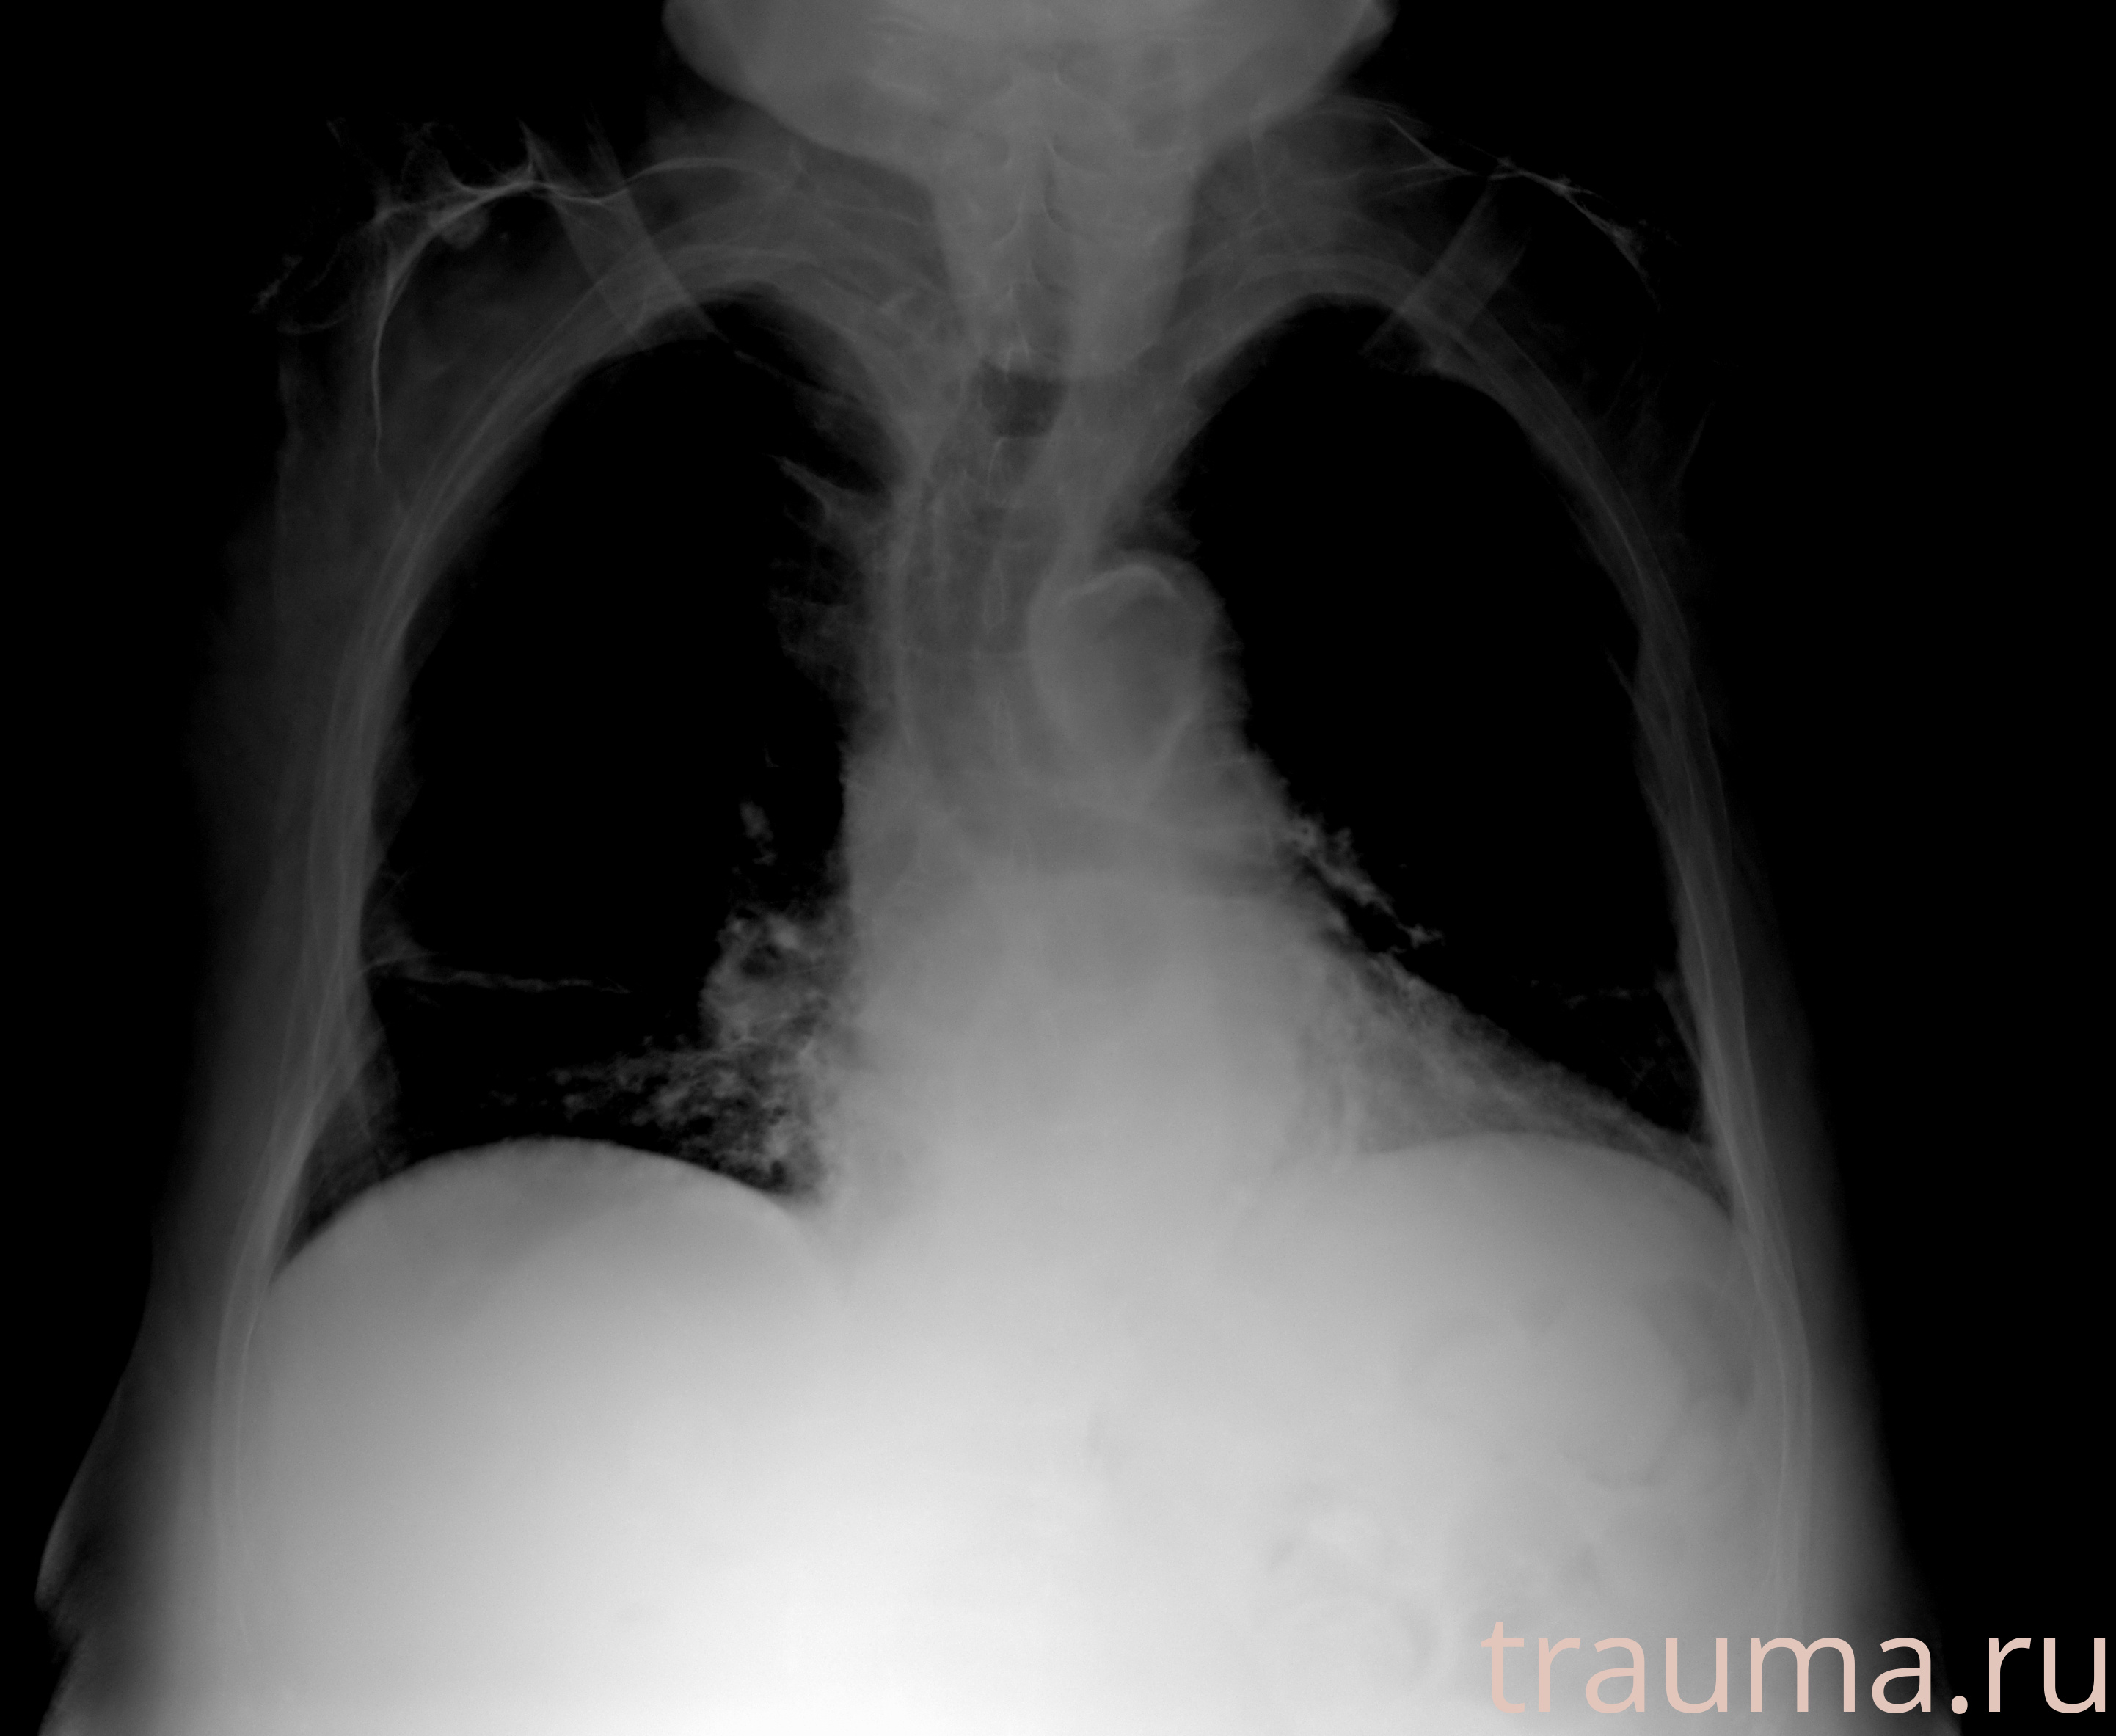

Рентгенограммы

Рентген на дому: по вашему адресу приезжает врач-рентгенолог, травматолог-ортопед с мобильным рентгеновским аппаратом, проводит диагностику травмы или заболевания, делает необходимые рентгенограммы, дает рекомендации по дальнейшему лечению. Получить качественные снимки в домашних условиях возможно благодаря уникальной методике, разработанной МосРентген Центром для института  Склифосовского